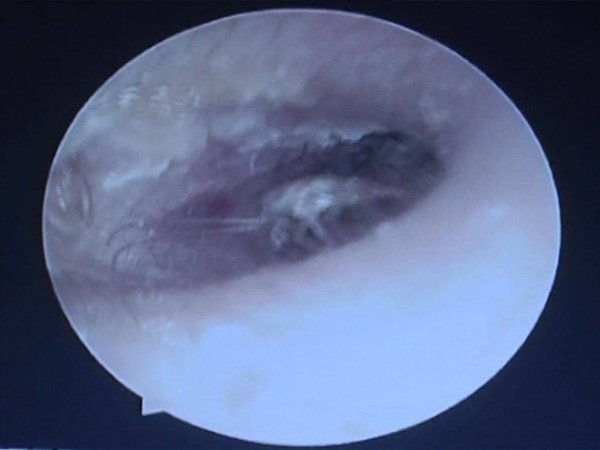

డాక్టర్ పరీక్ష చేసి చూసినప్పుడు ఏదో తమ వైపు చూస్తున్నట్టుగా అనిపించింది. చెవిలో మొత్తానికి ఏదో కీటకం ఉందని భావించి లోతుగా పరీక్షించారు. ఆశ్చర్యపోవడం డాక్టర్ల వంతైంది. అక్కడ బతికున్న బొద్దింకల కుటుంబం రాజ్యమేలుతుంది.

వెంటనే ఆపరేషన్కు..

వెంటనే అతడికి అనస్థీషియా ఇచ్చి డాక్టర్లు ఒక్కొక్క బొద్దింకను చెవిలోంచి తీయడం మొదలుపెట్టారు. సర్జరీ ముగిశాక మొత్తం 26 బయటపడ్డాయి. యాక్! తల్చుకుంటే వెగటుగా ఉంది కదూ! బాధాకరమైన విషయం ఏమిటంటే అన్నీ బతికే ఉండడం కాదు బాగా యాక్టివ్గా ఉన్నాయి.